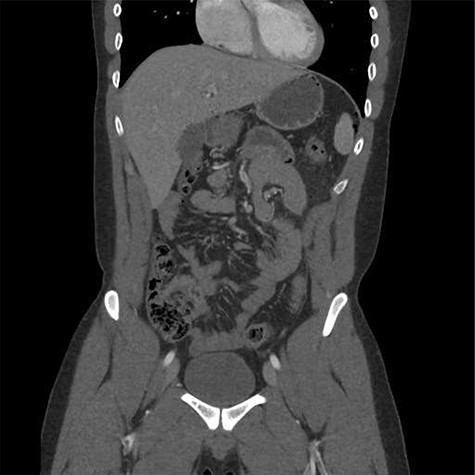

A chest X-ray did not show obvious pneumoperitoneum and a computed tomography scan demonstrated free gas in the abdomen with no solid organ injury (Figs 1 and 2). The patient was taken to theatre for a laparotomy and a 2 cm jejunal perforation was found on the mesenteric border, 10 cm from the duodenal–jejunal flexure. No other injuries were identified. A primary two-layer repair of the jejunum was performed with 4–0 polydioxanone suture. His postoperative recovery was unremarkable and was discharged after opening his bowels and tolerating oral intake at postoperative day 6.

Axial computed tomography image demonstrating mesenteric stranding and free gas locules.